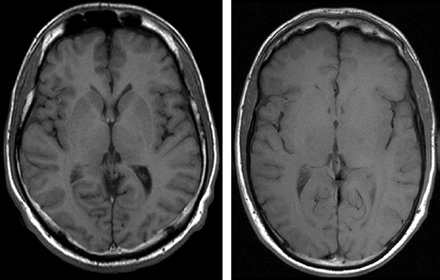

Apparently, gray-to-white matter contrast is reduced in spin-echo T1 imaging at 3T (30) when compared with 1.5T (Fig 6). There are several factors contributing to this observation. T1 times of gray and white matter lengthen and converge at higher fields (31–33). Moreover, shielding effects induced by eddy currents prevent central parts of the image from being properly excited (16), which results in reduced signal intensity of the basal ganglia region. In addition, magnetization transfer effects are enhanced at higher B0, thus reducing signal intensity and contrast. There are several ways to compensate for these effects. For example, inversion recovery sequences appear very well suited if one is only interested in increasing gray to white matter contrast (Fig 7). The inversion pulse, however, interferes with visualization of contrast enhancement following gadolinium administration. Enhancing lesions may not be visible (Fig 8), because in inversion recovery sequences, unlike conventional T1 spin-echo sequences, the tissue with the shortest T1 does not necessarily exhibit the brightest signal intensity, depending on T1. Therefore, inversion recovery sequences are not quite useful for comparative pre- and postcontrast T1 spin-echo imaging, regardless of B0. A different approach to increase gray-to-white matter contrast during T1-weighted spin-echo imaging at both field strengths is to reduce the excitation flip angle (34). Although this reduces SNR slightly, the gain in gray-to-white matter contrast is obvious and more pronounced at 3T (Fig 9). The effect can be predicted from theoretical calculations (35) by using known T1 and T2 relaxation times of gray and white matter (33) but is empirically larger than the theoretical predictions at 3T, probably because of shielding and magnetization transfer effects (34).

Left, T1 spin-echo image at 1.5T (TR, 600 ms; TE, 14 ms; bandwidth, 90 Hz/pixel; section thickness, 5 mm; matrix, 256 × 192; FOV, 220 × 220 mm2; flip angle, 90°). Right, T1 spin-echo at 3T (TR, 700 ms; TE, 10 ms; section thickness, 5 mm; 19 sections; bandwidth, 200 Hz/pixel; matrix, 256 × 192; FOV, 220 × 220 mm2; flip angle, 90°), which is indicative of the reduced gray-to-white matter contrast at higher fields.

Turbo inversion recovery (TIR) sequence at 1.5T (left: TR, 8770 ms; TE, 92 ms; TI, 300; matrix, 512 × 256; section thickness, 3 mm; FOV, 220 × 220 mm2; bandwidth, 130 Hz/pixel) and 3T (right: TR, 8890 ms; TE, 95 ms; TI, 300; all other parameters equal), which demonstrates clear depiction of gray and white matter at both field strengths.